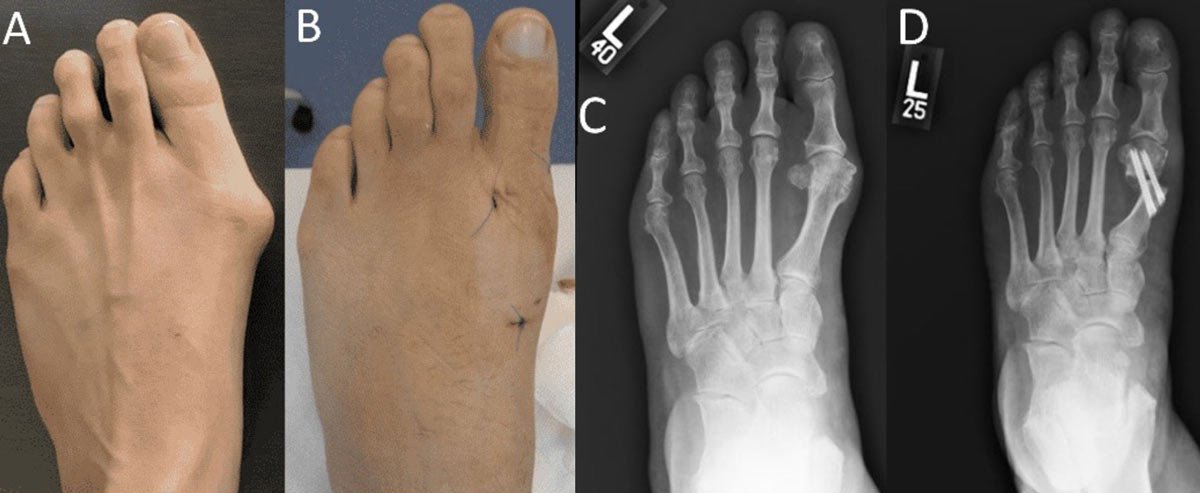

تحدث هذه الحالة عندما ينحرف الإصبع الكبير باتجاه الأصابع المجاورة، مما يؤدي إلى ظهور نتوء عظمي بارز (Bunion) عند قاعدة الإبهام من الجهة الداخلية للقدم. ومع الوقت، قد يزداد التشوه ويصاحبه ألم والتهاب وصعوبة في ارتداء الأحذية.

في هذه التقنية يتم إجراء شقوق صغيرة جدًا (3–4 مم) بدلاً من الشق الجراحي التقليدي الكبير، ويتم استخدام أدوات دقيقة لإعادة محاذاة العظام وإزالة النتوء العظمي، ثم تثبيت العظام بمسامير خاصة.

يعتمد اختيار الطريقة الجراحية على درجة الانحراف وزوايا الأشعة. وهي قياسات دقيقة يتم تحديدها من خلال الأشعة السينية للقدم أثناء الوقوف.

يقوم الطبيب بقياس ما يُعرف بـ زاوية انحراف إبهام القدم (Hallux Valgus Angle – HVA)، وهي الزاوية بين عظمة المشط الأولى وإصبع القدم الكبير، وكذلك زاوية التباعد بين عظمتَي المشط الأولى والثانية (Intermetatarsal Angle – IMA).

هذه الزوايا تُحدد درجة التشوه بدقة، وبناءً عليها يتم اختيار التقنية الجراحية المناسبة، سواء كانت تصحيحًا بسيطًا أو تدخلًا أعمق لإعادة ضبط محور العظمة.